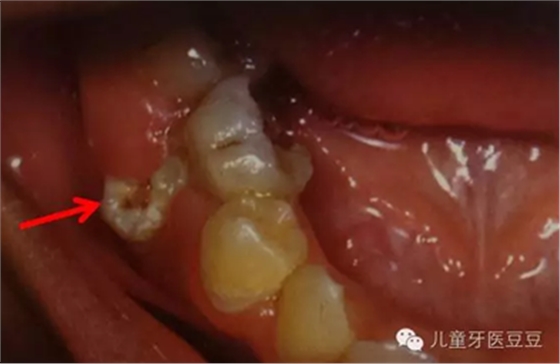

有時孩子的乳牙齲壞嚴(yán)重,已經(jīng)影響到了牙髓必須進(jìn)行根管治療(主要目的是通過治療,去除已經(jīng)壞死感染的牙髓組織,減少它們對牙齒根尖的不良影響,并使用可以吸收的材料將根管沖洗充填)。家長常常擔(dān)心乳牙要是沒有了牙髓,是不是恒牙就不能正常替換;是不是恒牙也就沒有了牙髓。這些都是誤解,乳牙和恒牙有自己獨(dú)立的牙髓系統(tǒng),即使乳牙沒有牙髓恒牙也可以替換。相反如果乳牙反復(fù)感染(這是往往牙髓早已壞死也是沒有正常的牙髓的),導(dǎo)致根尖周炎則會影響恒牙的發(fā)育和萌出。

乳牙反復(fù)根尖發(fā)炎導(dǎo)致繼承恒牙發(fā)育不良